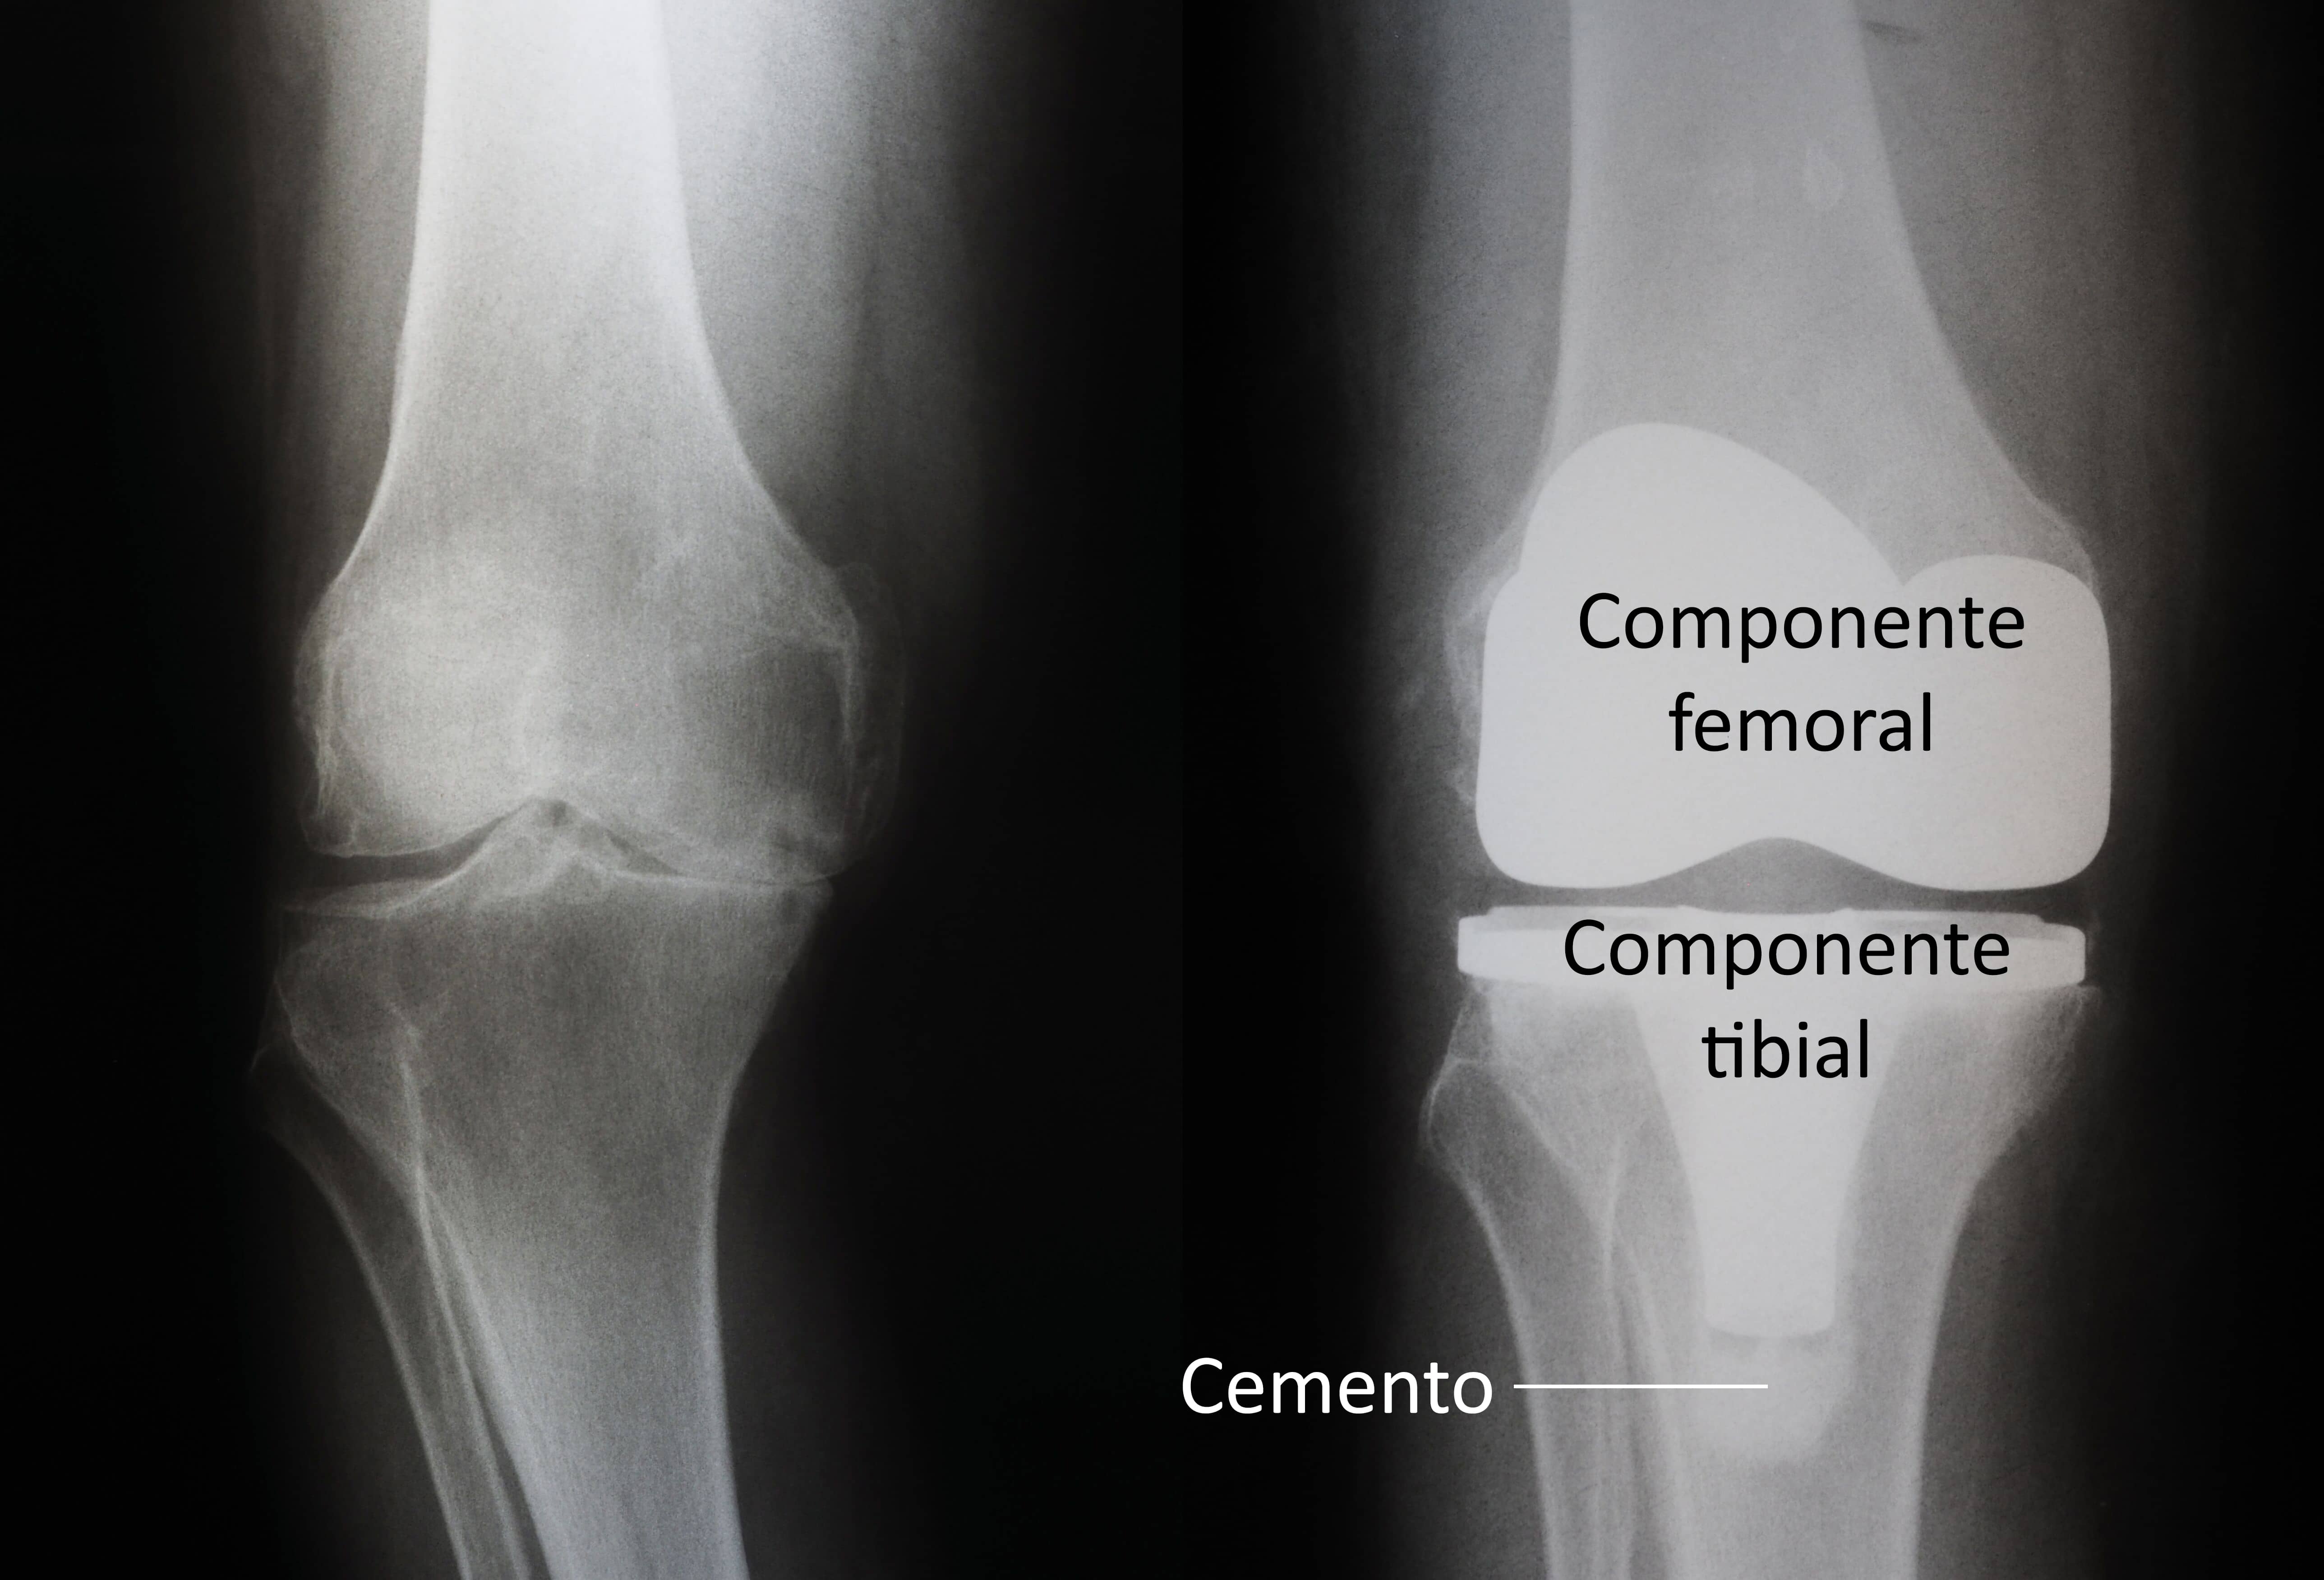

(Izquierda) Osteoartritis grave. (Derecha) El cartílago con artritis y el hueso subyacente se han quitado y resuperficializado con implantes de metal en el fémur y la tibia. Se ha colocado un espaciador de plástico entre los implantes. El componente rotuliano no se muestra para ofrecer claridad.

Se usan diferentes tipos de implantes de rodilla para satisfacer las necesidades de cada paciente.

(Izquierda) Una radiografía de una rodilla con artritis grave. (Derecha) Una radiografía de un reemplazo total de rodilla. Tenga en cuenta que el espaciador de plástico insertado entre los componentes no se muestra en una radiografía.